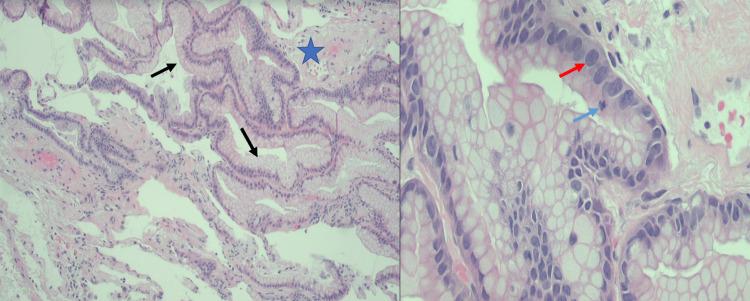

This is a case of a 92-year-old female with multiple hospitalizations for dyspnea on exertion and hypoxemia. Her symptoms were initially thought to be secondary to pneumonia, and on subsequent admission, culture-negative endocarditis. A computed tomography (CT) of the chest was remarkable for numerous bilateral lung nodules of varying size, some of which had a cavitary appearance raising concern for septic emboli. While a transthoracic echo was unremarkable, a transesophageal echo found a small 3 mm echodensity at the tip of the right coronary leaflet of the aortic valve and a possible mobile echodensity on the tricuspid valve leaflet. These findings further supported a clinical diagnosis of endocarditis with septic emboli in the lungs. Initial bronchoscopy yielded an unremarkable biopsy and a bronchial alveolar lavage with the growth of . During a subsequent hospitalization, a repeat bronchoscopy with transbronchial biopsy revealed a final diagnosis of invasive pulmonary mucinous adenocarcinoma. This case highlights a unique presentation of mucinous adenocarcinoma of the lung initially masquerading as septic emboli, resulting in a delay in the final diagnosis.

这是一例92岁女性患者,因劳力性呼吸困难和低氧血症多次住院。她的症状最初被认为继发于肺炎,随后入院诊断为血培养阴性的心内膜炎。胸部计算机断层扫描(CT)显示双侧有许多大小不一的肺结节,其中一些有空洞形成,令人担心是脓毒性栓子。经胸超声心动图检查无异常,但经食管超声心动图发现主动脉瓣右冠状动脉瓣叶尖端有一个3毫米的小回声密度,三尖瓣叶上可能有一个可移动的回声密度。这些发现进一步支持了伴有肺部脓毒性栓子的心内膜炎的临床诊断。初次支气管镜检查活检结果无异常,支气管肺泡灌洗培养出……。在随后的一次住院期间,再次进行支气管镜检查并经支气管活检,最终诊断为浸润性肺黏液腺癌。该病例突出了肺黏液腺癌一种独特的表现形式,最初伪装成脓毒性栓子,导致最终诊断延迟。